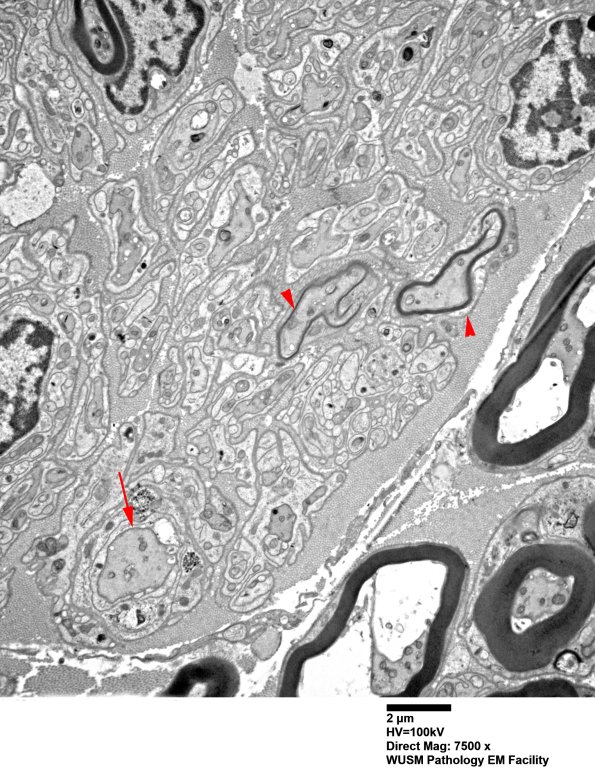

Electron microscopy demonstrates that the patchy zones are composed of Schwann cells, unmyelinated axons and developing thinly myelinated axons (arrowheads) with an axon (arrow) large enough to represent a pre-myelinated axon. (electron micrograph)